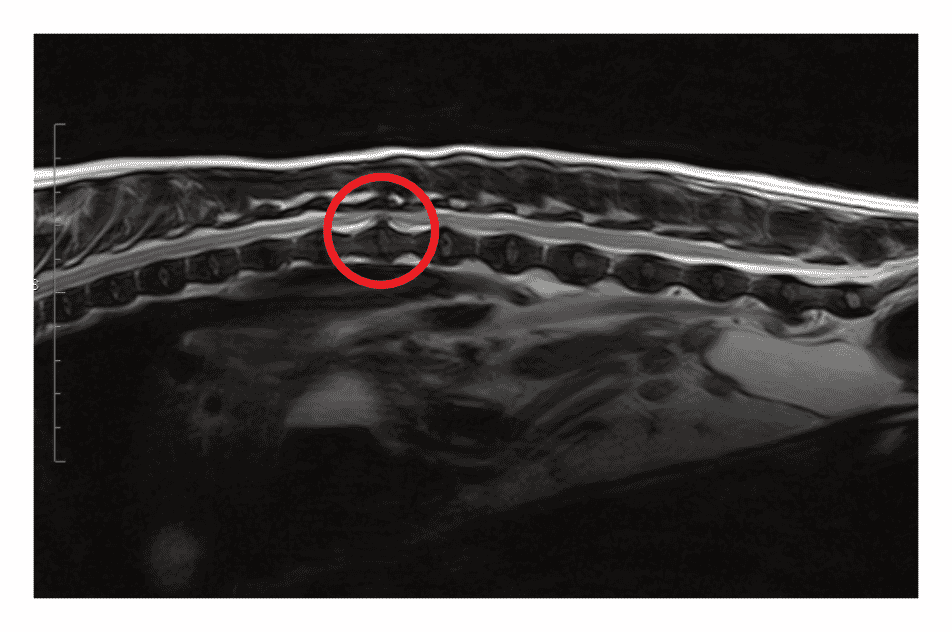

Magnetic resonance imaging has proven to be very valuable in the assessment of pathology within the spine (Weiner and Patel, 2008). MRI uses the body’s natural magnetic properties to produce detailed images. It can be used for all parts of the body, but in veterinary medicine we mostly use it to obtain images of the brain and spinal cord. There are no known biological hazards of using MRI as it uses radiation from the radiofrequency range which is found all around us, causing no harm to tissues. This differs from radiography and computed tomography (CT). It is important to check whether patients needing an MRI have any pacemakers, metal clips or metal valves as these will pull towards the magnetic field, which can be dangerous. Metal joint prostheses or implants, however, can be put through the MRI scanner, but these usually cause artefacts on the image (Berger, 2002). MRI will allow you to identify whether there is any pathology in the spinal cord and gives very detailed images showing how much the spinal cord is being compressed and at what location (Figure 1).